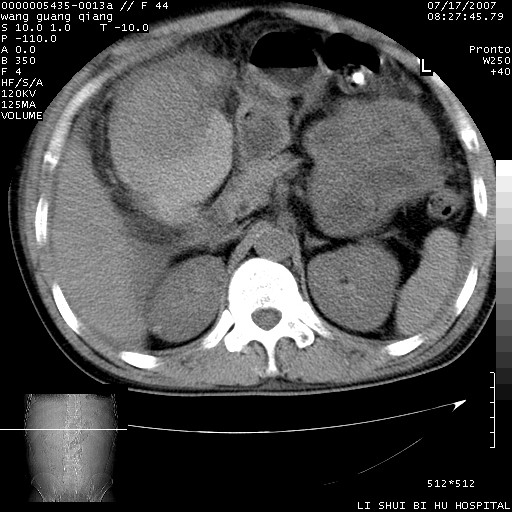

以下是引用dyqct在2007-7-18 10:46:00的发言:[br]胆囊明显增大,壁增厚,明显强化;后下方见大片高密度区,ct值68hu,无强化,周围见多数条纹状高密度影,边界不清。双膈下间隙、肝肾隐窝见带状及片状低密度区。[br]右侧胸壁后缘亦见新月形水样密度区。[br]考虑:1、急性胆囊炎伴周围出血;[br] 2、少量腹水、右侧少量胸腔积液。[br][br][本贴已被 dyqct 于 2007-7-18 10:48:47 修改过]